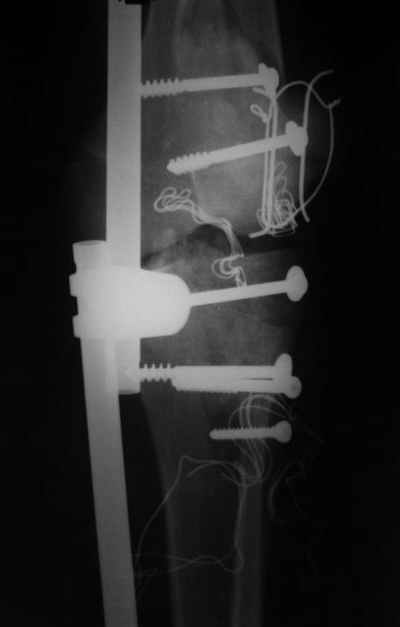

Вид раны на сегодня...

4 cутки после травмы.